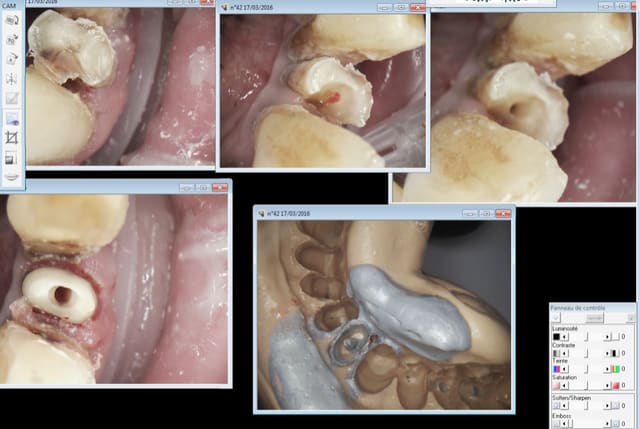

42, endo taille empreinte provisoire 1H.

Je "fidélise" la 43. Trop chiante à soigner pour un tarif de merde. -)

Capture d e cran 2016 03 17 11.17 - Eugenol

Capture d e cran 2016 03 17 11.15 - Eugenol